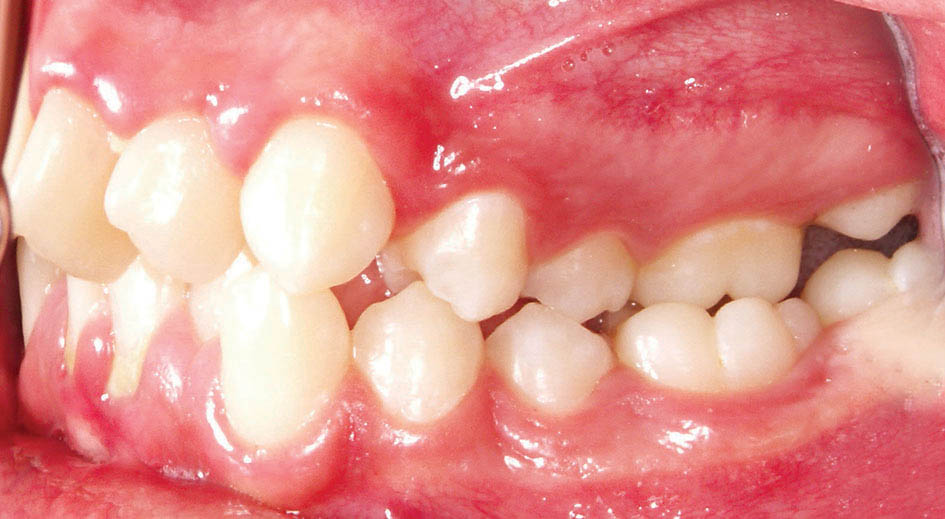

طی سالهای اخیر بعد از ارائه براکتهای Self Ligating تحقیقاتی انجام شده است. به دلیل اعمال نیروی ملایم در این سیستم براکتی، فعالیت سلولهای استخوان ساز بیشتر میشود. با افزایش عرض بین کانینها چون استخوان سازی هم رخ میدهد، شاهد حداقل برگشت درمانهای ارتودنسی هستیم (شکل 66-3 الی 69-3).

شکل 69-3: قوس پایین بعد از درمان با براکتهای self ligating